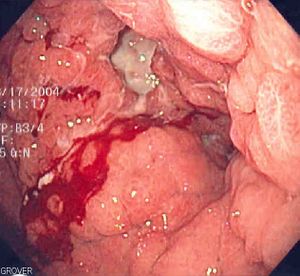

| A suspicious stomach ulcer that was diagnosed as cancer on biopsy and resected. Surgical specimen. | |

ـ التنطير الهضمي والخزعة: مع التطور الكبير في مجال صناعة المناظير الضوئية الليفية المرنة flexible fiberoptic endoscopes، صار من السهل إجراء فحص كامل ودقيق لمخاطية المعدة، ومشاهدة التغيرات المرضية، ومنها سرطان المعدة، مباشرة، وكذلك أخذ خزعات متعددة منها من أجل التشخيص النسيجي. ويجب أخذ 4 إلى 6 خزعات من أي آفة مشبوهة في المعدة لرفع دقة التشخيص.